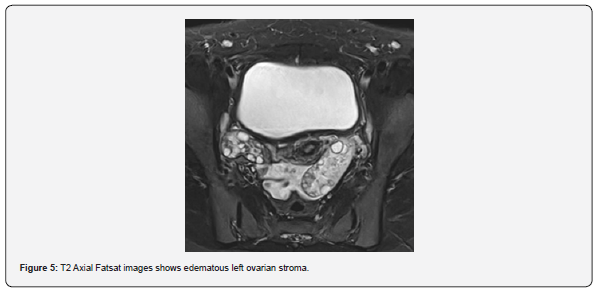

The patient is a 12-year-old girl who presented to emergency department with severe left-sided abdominal pain associated with persistent vomiting for the past two days. On physical examination left flank tenderness was noted with radiation to suprapubic area, there was no diarrhea or fever. Pelvic ultrasound with Doppler demonstrated bilaterally enlarged ovaries with small follicles with a markedly enlarged left ovary showing reduced vascularity and no evidence of identifiable ovarian cyst (Figures 1-4). Magnetic resonance imaging (MRI) demonstrated bilateral ovarian enlargement with multiple small follicles, assuming polycystic ovarian morphology. The left ovary was significantly enlarged, positioned posterior to the uterus and showed stromal edema with decreased post-contrast enhancement compared to contralateral side, findings consistent with ovarian torsion (Figures 5-10).

This finding demostrates the limitations of imaging in detecting small or subtle ovarian lesions and highlights the importance of clinical judgement together with supportive imaging findings when evaluating suspected ovarian torsion. Polycystic ovarian morphology in pediatric patients should also be considered a potential risk factor for ovarian torsion, even when a dominant cyst is not present. Additionally, MRI demonstrated bilateral polycystic ovarian morphology, with greater enlargement of the affected ovary. Increased ovarian volume associated with polycystic morphology has been reported as a possible predisposing factor for ovarian torsion. In this case, asymmetric ovarian enlargement in the setting of polycystic morphology may have increased the susceptibility of the affected ovary to torsion.